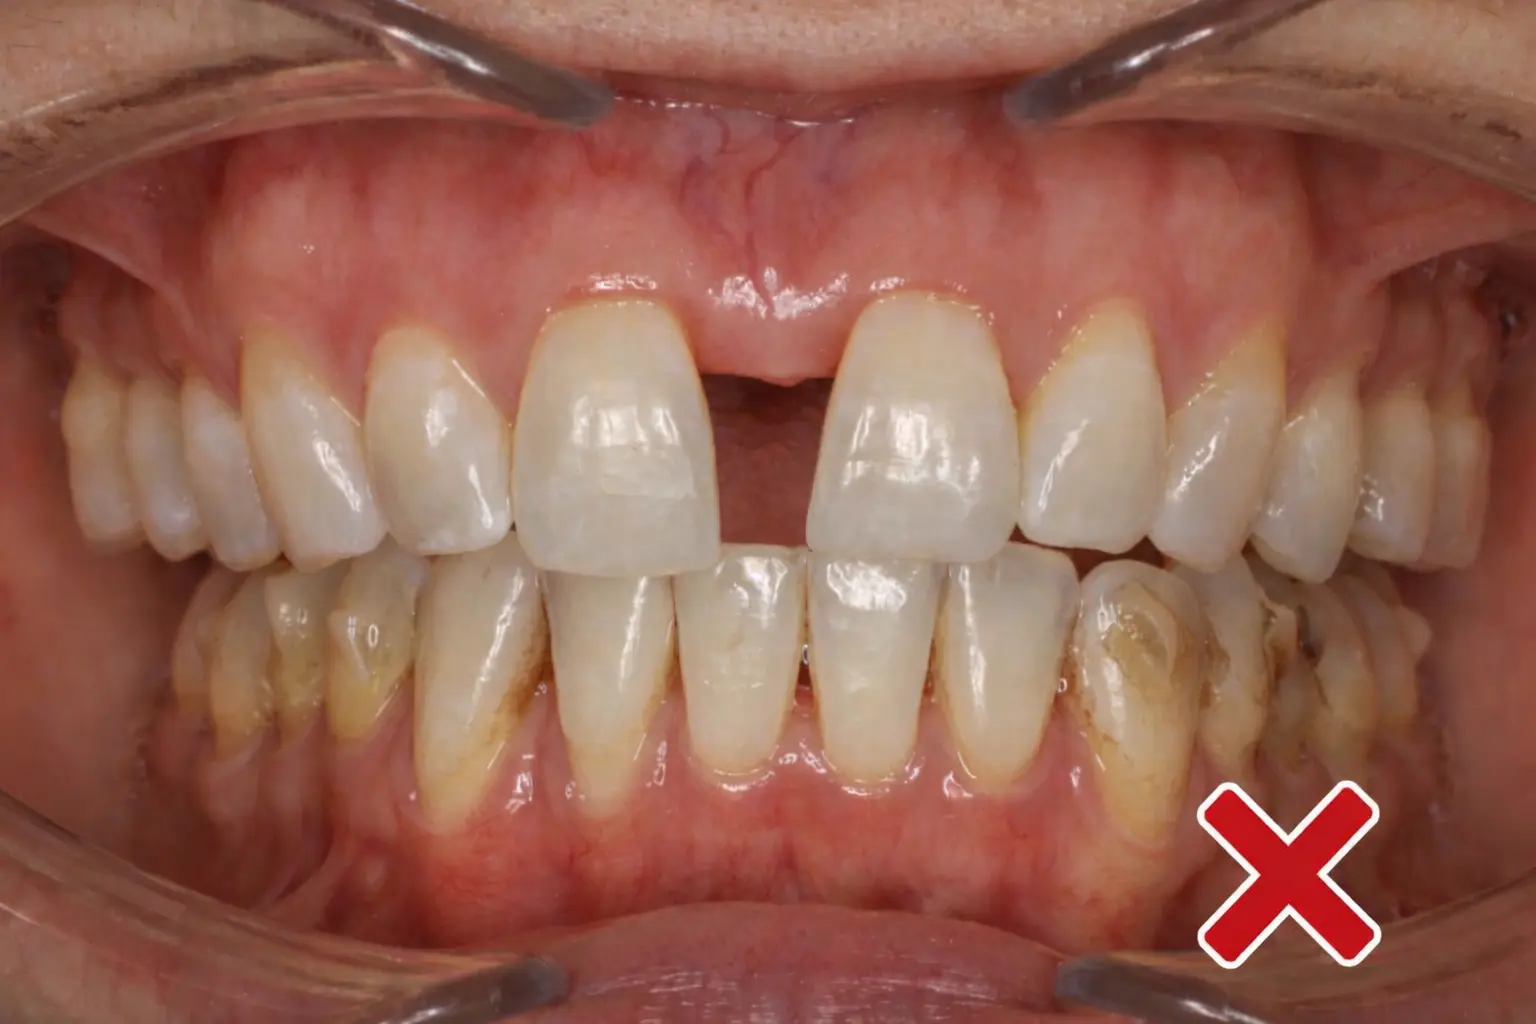

Dental models and coronal X-ray showing tooth-borne expansion with outward tipping instead of true skeletal widening

As shown in the image on the left, a tooth-borne expander can create a wider palate and more tongue space, but the X-ray demonstrates that much of this change is achieved by pushing the teeth outward rather than producing true skeletal expansion.